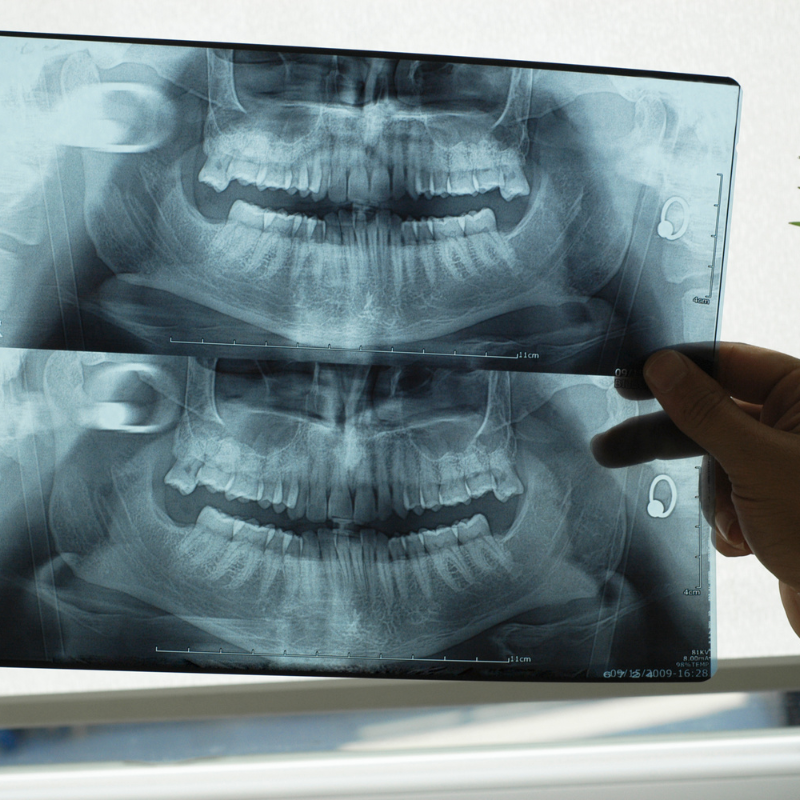

Η σύγχρονη οδοντιατρική ακτινογραφία αποτελεί την αιχμή του δόρατος στην οδοντιατρική διάγνωση. Τα σύγχρονα συστήματα ψηφιακής πανοραμικής ακτινογραφίας εξασφαλίζουν εξαιρετική ευκρίνεια εικόνας με την ελάχιστη δυνατή έκθεση σε ακτινοβολία. Στο ιατρείο μας στην Αθήνα, η ακτινογραφία δοντιών πραγματοποιείται με τον πλέον σύγχρονο εξοπλισμό, προσφέροντας άμεση διαθεσιμότητα αποτελεσμάτων και δυνατότητα ψηφιακής επεξεργασίας για βελτιστοποίηση της διάγνωσης.

Η πανοραμική ακτινογραφία δοντιών προσφέρει μια ολοκληρωμένη εικόνα της στοματικής κοιλότητας. Το οδοντιατρικό κέντρο μας διαθέτει υπερσύγχρονο εξοπλισμό για ψηφιακές πανοραμικές ακτινογραφίες στην Αθήνα, παρέχοντας πλήρη απεικόνιση σε μία μόνο λήψη. Η τεχνολογία αυτή είναι ιδανική για την αξιολόγηση της συνολικής οδοντικής κατάστασης, τον εντοπισμό έγκλειστων δοντιών και τον προεγχειρητικό σχεδιασμό.